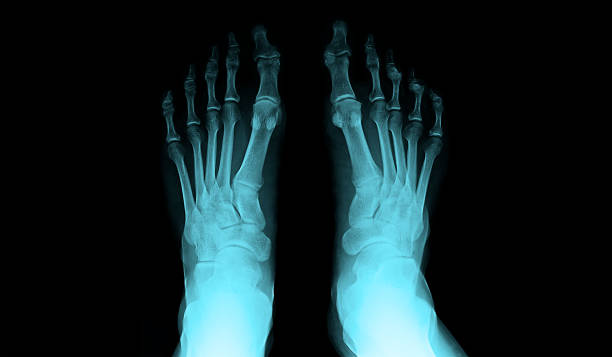

발뒤꿈치가 아픈 이유 1. 족저근막염

발뒤꿈치가 아픈 이유 첫 번째는 족저근막염입니다. 족저근막은 발뒤꿈치 뼈에서 시작하여 발바닥 앞쪽으로 연결되는 두껍고 강한 섬유질 띠입니다. 족저근막은 우리 몸의 중요한 역할을 하는데 아치 모양의 모양새는 우리 몸의 체중을 흡수하기 때문에 걷는 데 중요한 역할을 할 수 있습니다. 족저근막염은 이러한 족저근막에 반복되는 충격으로 근막을 둘러싸고 있는 콜라겐이 변성하면서 염증이 생긴 것을 의미합니다.

이러한 증상은 원래부터 평발이거나 걸음걸이나 생활습관 등으로 발이 변형되며 구조적으로 이상이 생겨서 문제가 생길 수도 있지만 기본적으로 하체 사용을 무리하게 하다보면 문제가 생기게 됩니다. 족저근막염 통증은 개인에 따라 다르지만 기본적으로 발뒤꿈치에 통증을 느끼게 되고 특히 아침 기상후 첫 걸음부터 통증이 나기 때문에 조기에 치료를 받는 것이 중요합니다.